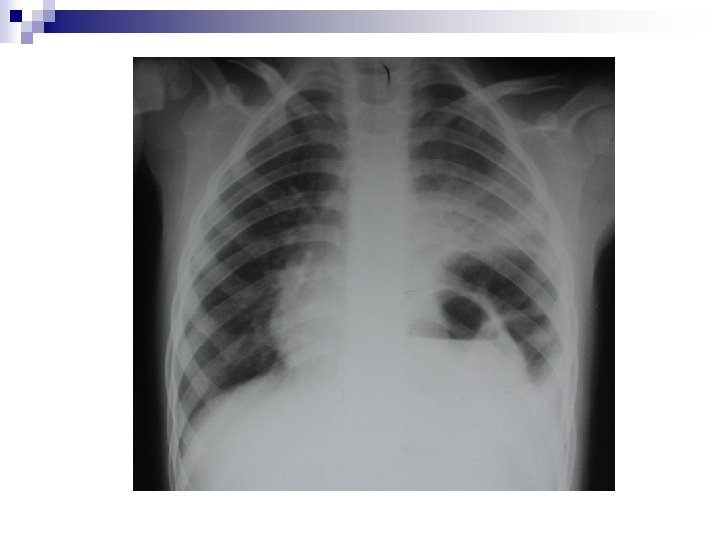

Signes R* Télé thorax f+p * Présence de multiples images aériques Directs * SNG remontant en hameçon * Compression par déviation du cœur Indirects * Défect diaphragmatique * Vacuité abdominale